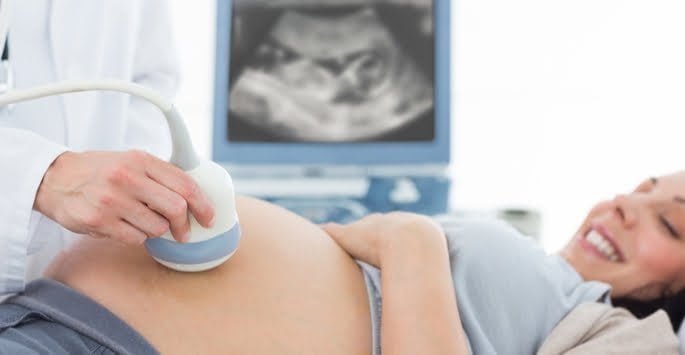

Transvaginal pelvic ultrasound is a diagnostic tool that we can use to check for an ectopic pregnancy. We use a device that lets us take pictures of the vagina and the surrounding area.

Ultrasound is a name for the high-frequency soundwaves used. The technician uses a device called a transducer that emits ultrasound waves. The waves bounce off the different tissues and are then converted into electrical impulses that form a picture.

Transvaginal pelvic ultrasound is an outpatient procedure that can be performed in the comfort of our office. The transducer will display images in “real time,” and the technician will also take still photographs.